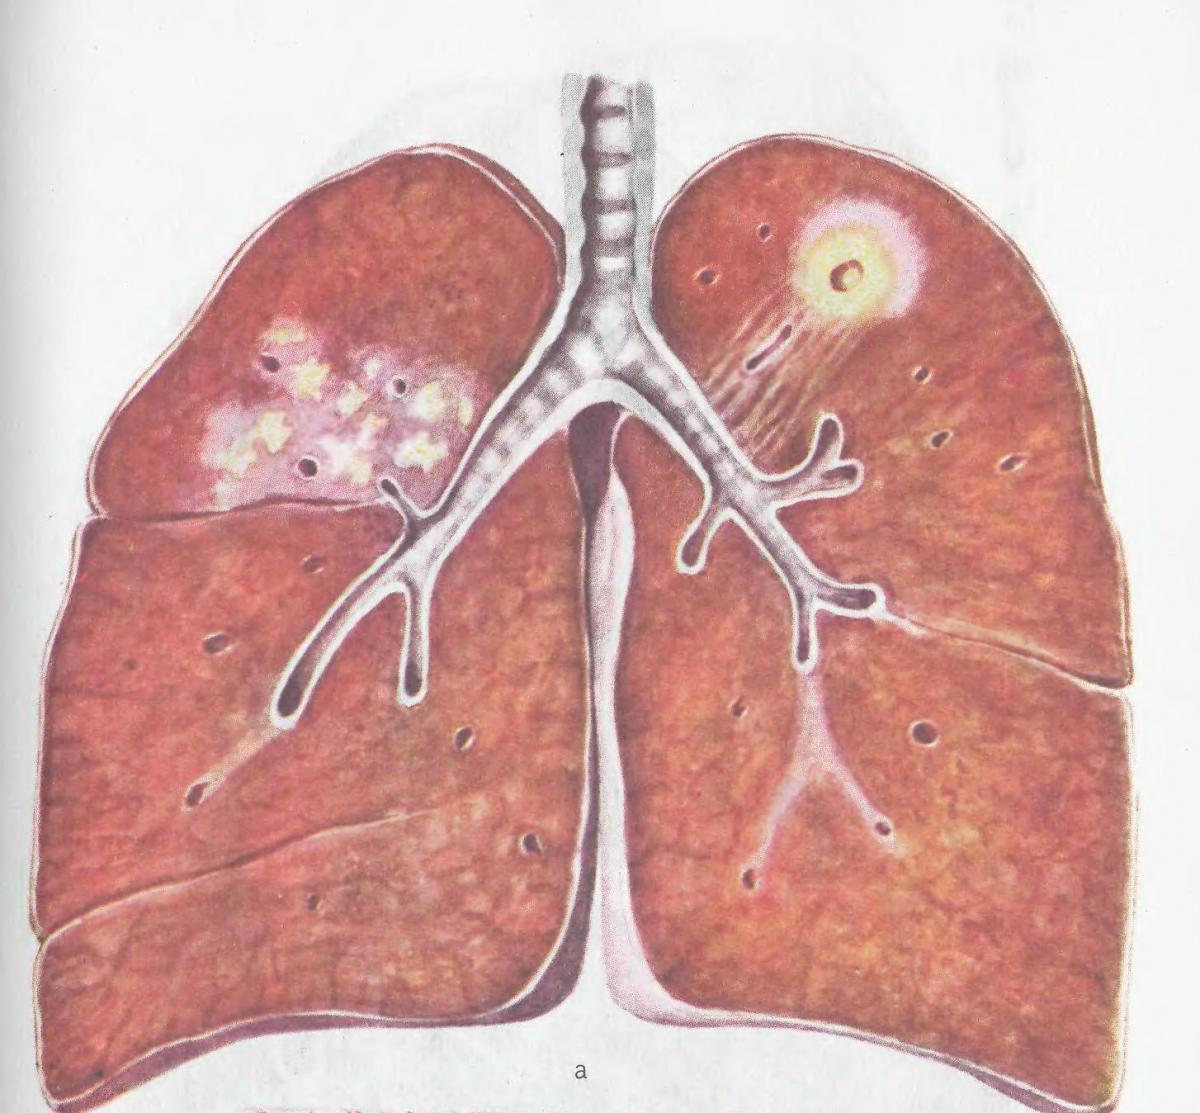

Иллюстрации по теме очагового и инфильтративного туберкулеза